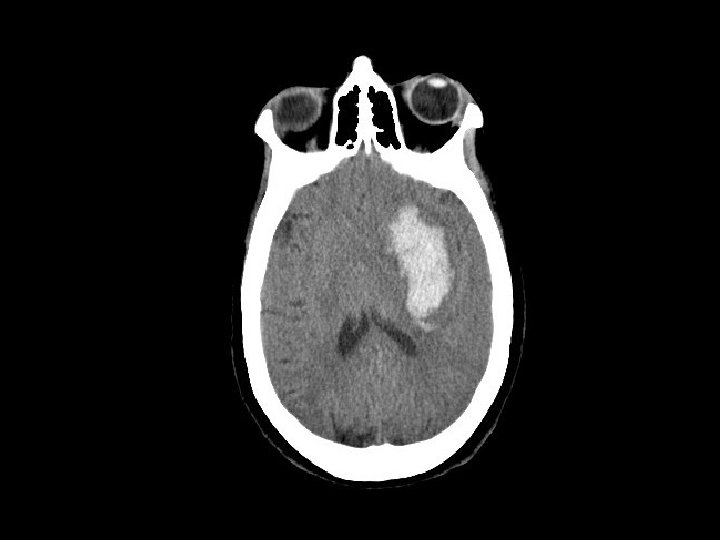

Máu tụ ngoài màng cứng (EDH) • Chảy máu ngoài màng cứng – Thường do động mạch (động mạch màng não giữa) nhưng cũng có thể do chảy máu tĩnh mạch • CT: hình tụ máu thấu kính lồi – Xuất huyết nằm khư trú do hạn chế trong khoảng giữa màng cứng và sọ • 5 -15% bệnh nhân CTSN có tụ máu ngoài màng cứng

Máu tụ ngoài màng cứng • Có nguy cơ tăng khối choán chỗ và gây thoát vị liềm não (giãn đồng tử) – “khoảng tỉnh và sau đó tử vong” • Quan sát được tụ máu ngoài màng cứng • Tụ máu ngoài màng cứng gây choán chỗ cần can thiệp phẫu thuật